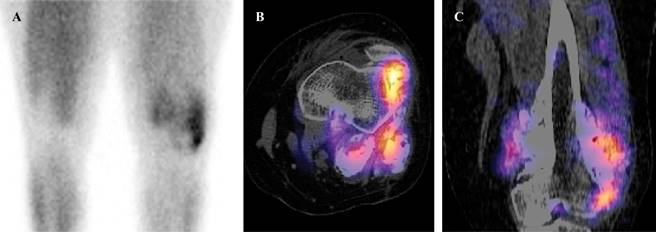

Nuclear Medicine: Gamagraphy with 99mTc-MIBI reported a bone lesion, with extension to adjacent soft tissues, with an abnormal increase in the radiopharmaceutical. The greater uptake of the lesion was towards the lateral región. The SPECT/CT reported an exophytic bone lesion, located in the metaphysis, with heterogeneous appearance, and abnormal increase in the radiopharmaceutical. The lesion showed multiple positive focal zones (Figure 4).

Figure 4: Gammagraphy (A) There is abnormal increase in the radiopharmaceutical in soft tissues. The greater uptake of the lesion was towards the lateral region. SPECT/CT axial (B) and sagittal (C). Presence of multiple focal zones of abnormal increase in the radiopharmaceutical.